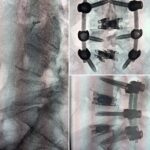

T/PLIF Solutions

T/PLIF

Heights 7mm* expanding to 17mm*

Width 12mm expanding to 21mm

0°, 8°, 12° and 15° Lordosis*

TLIF